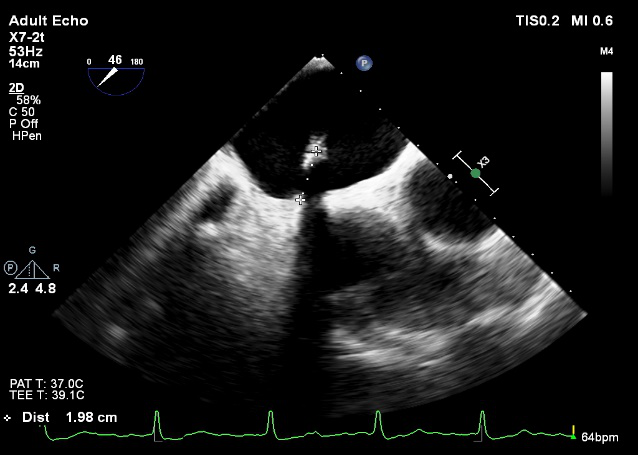

术中超声

确定房间隔穿刺点:靠后

2D视图下测量大鞘长度2cm

3D视图打开夹子

X-plane:下第夹子尝试捕获2区

X-plane:测量前叶长25mm,后叶长14.2mm

X-plane:计算前叶捕获长度8mm,后叶捕获长度7mm

3D视图下观察二尖瓣双孔形态

3D-color:残余少量返流